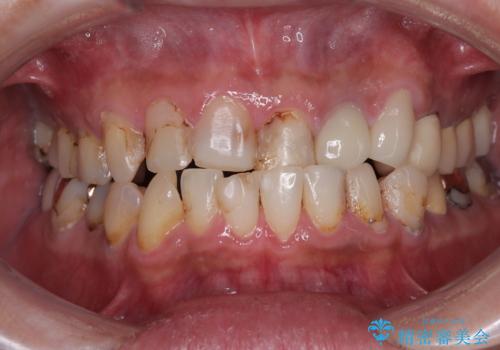

- 前歯などに、むし歯でボロボロになった歯があるとのことで来院された患者様です。

むし歯により歯冠が崩壊してから長いこと経過しているとのことで、歯を失ったことによる他の歯への影響はあまりないと判断されたため、審美領域である上顎前歯部のみにインプラント補綴治療を行うこととしました。

崩壊した歯は全て抜去し、他人から見える位置の歯はセラミッククラウンが装着され、整った口腔環境となりました。